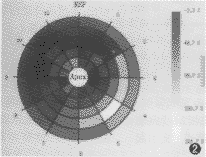

2. 数据分析:电影资料的动态分析(左心室):(1)心壁分区:自心底二尖瓣口层面向心尖层面连续切层扫描5~8层,以心长轴为中心放射状将左心室前、侧、后壁和室间隔分为8~12段,共约40~96个节段(图1)。(2)自动勾画出每幅图像心壁的内外缘(ARGUS软件自动完成),手动修正。(3)启动分析软件(ARGUS),主要分析内容包括:①各节段心肌的增厚率[ΔT=(TS-TD)/TD×100%]。ΔT为心肌增厚率;TS为收缩末期心室壁厚度;TD为舒张末期心室壁厚度],并给出各部分心壁厚度及增厚率之间的灰阶差异直观对比示意图,即所谓“牛眼”图(图2)。②心腔容积:包括舒张末期容积(EDV)和收缩末期容积(ESV)(V=πD2L/6 ≈D3;D为左室短轴)。③自动画出左室容积-时间变化曲线图。④每搏心输出量(SV)。⑤心室射血分数[EF=(EDV-ESV)/EDV×100%][1]。⑥心肌收缩持续时间。

图2 牛眼图。由5~8层同心圆组成,分别表示自心尖到心底的连续心室切层,被8~12条线划分为40~96个扇区。REF为参考范围,Apex为心尖

ARGUS自动心功能分析软件能自动测量出左室各节段心壁收缩末期和舒张末期心肌厚度,以及心肌增厚率,前者能精确反映心肌肥厚的部位和肥厚程度,后者可反映心肌收缩功能。另外,对肥厚心肌以室间隔、左心室前壁好发,不均匀分布的特点,以及心肌收缩增厚的情况,可以从软件所描绘的各节段心壁间心肌厚度和心肌增厚率差异的黑白灰阶对比示意图上,直观、整体地显示出来(图2)。统计结果显示:肥厚部位舒张末期心壁厚度的绝对值均≥15 mm,其与左心室后壁同期厚度比值≥1.5。心肌增厚率下降,其中非匀称型肥厚型心肌病患者的心肌增厚率显著低于心尖肥厚型和正常组(t=15.1,P<0.01)。与正常组相比,心尖肥厚型心肌病心肌增厚率虽低于正常组,但两者差异无显著性意义(t=1.65,P>0.05)。与Richard等统计结果一致[1-4]。